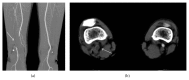

Cystic adventitial disease (CAD) is a rare cause of intermittent claudication and nonatherosclerotic conditions in middle-aged men without cardiovascular risk factors. The etiology of CAD is unclear; however, the direct communication between a cyst and a joint is presumed to be a cause. We herein report a case series of CAD of the popliteal artery (CADPA), in which patients were treated with surgical resection and vascular reconstruction. Although less invasive treatment modalities, including percutaneous cyst aspiration and percutaneous transluminal angioplasty, have been the subject of recent reports, these treatments have had a higher recurrence rate. Therefore, all of the CAPDA cases in the present series were treated surgically, which lead to good outcomes.